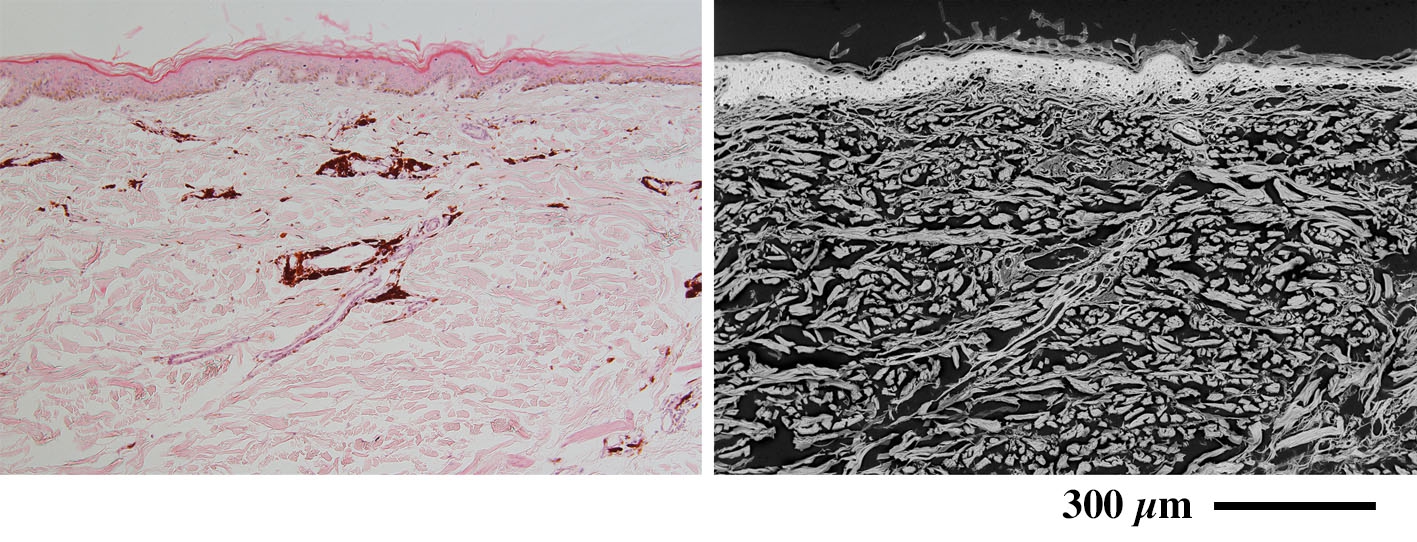

刺青 Tatoo

(左:パラフィン切片のヘマトキシリン・エオジン染色光顕像/右:低真空SEM像)

血管周囲に沈着した色素は反射電子密度が低く観察されます